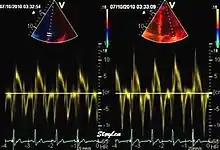

Tissue Doppler echocardiography (TDE) is a medical ultrasound technology, specifically a form of echocardiography that measures the velocity of the heart muscle (myocardium) through the phases of one or more heartbeats by the Doppler effect (frequency shift) of the reflected ultrasound. The technique is the same as for flow Doppler echocardiography measuring flow velocities. Tissue signals, however, have higher amplitude and lower velocities, and the signals are extracted by using different filter and gain settings. The terms tissue Doppler imaging (TDI) and tissue velocity imaging (TVI) are usually synonymous with TDE because echocardiography is the main use of tissue Doppler.

Like Doppler flow, tissue Doppler can be acquired both by spectral analysis (spectral density estimation) as pulsed Doppler[1] and by the autocorrelation technique as colour tissue Doppler[2] (duplex ultrasonography). While pulsed Doppler only acquires the velocity at one point at a time, colour Doppler can acquire simultaneous pixel velocity values across the whole imaging field. Pulsed Doppler on the other hand, is more robust against noise, as peak values are measured on top of the spectrum, and are unaffected of the presence of clutter (stationary reverberation noise).

This has become a major echocardiographic tool for assessment of both systolic and diastolic ventricular function. However, as this is a spectral technique, it is important to realise that measurement of peak values is dependent on the width of the spectrum, which again is a function of gain setting.

Pulsed wave spectral tissue Doppler has become a universal tool that is part of the general echocardiographic examination. Like any other echocardiographic measurement, measures by tissue Doppler should be interpreted in the context of the whole examination. The velocity curves are in general taken from the base of the mitral annulus at the insertion of the mitral leaflets, in the septal and lateral points of the four chamber view, and eventually the anterior and inferior points of the two-chamber views. For the right ventricle it is customary to use the lateral point of the tricuspid annulus only. Averaging peak velocities from the septal and lateral point has become common, although it has been shown that averaging all four points mentioned above, gives significantly less variability[3]

The method measures annular velocities to and from the probe during the heart cycle.

Annular velocities summarize the longitudinal contraction of the ventricle during systole, and elongation during diastole. Peak velocities are commonly used.